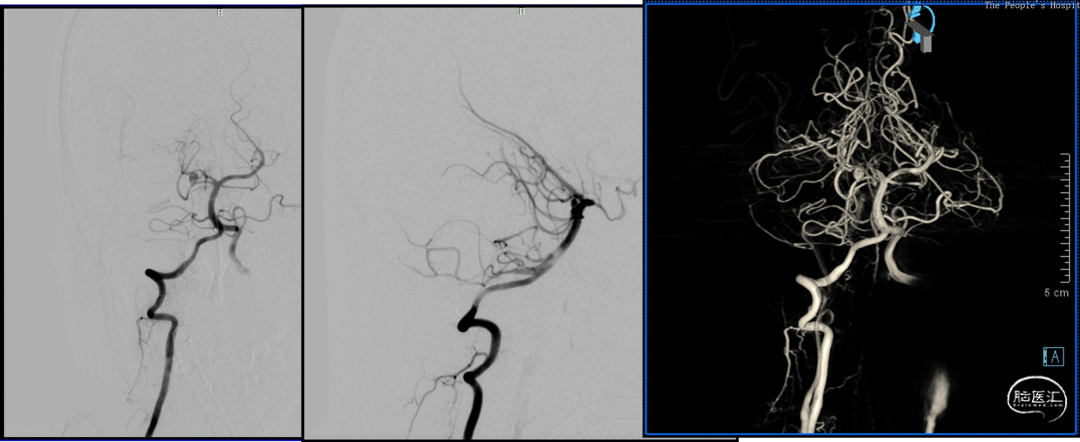

DSA

2023-08-30

前后循环3d融合寻找假性动脉瘤供血,

考虑为后交通动脉